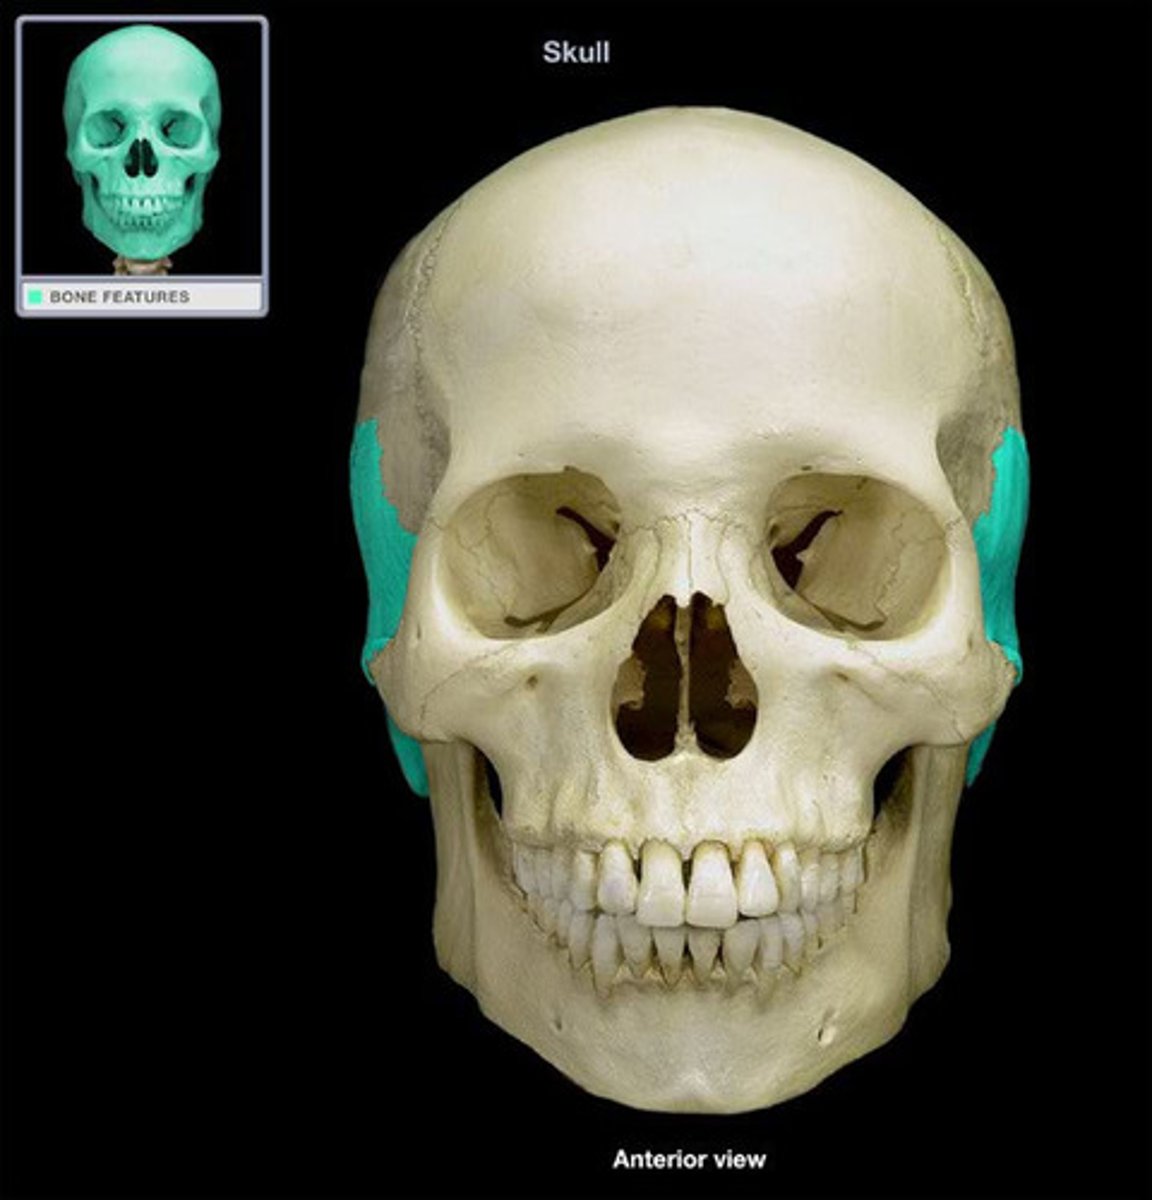

Zygomatic Bone

Zygomatic Bone